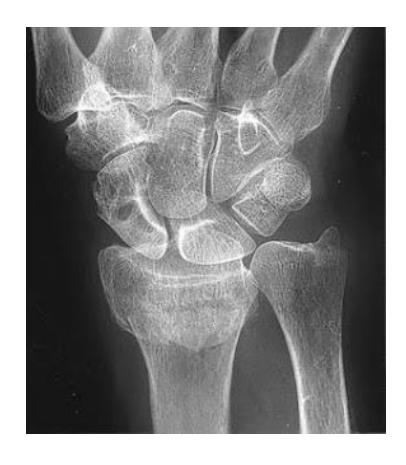

Scaphoid Fracture

Scaphoid Fracture Treatment

- Treatment: Thumb spica cast

What is the management of the finding in the image?

- Screw fixation